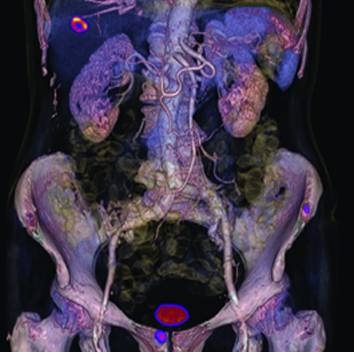

人体CT、PET、PET/CT图像的对照(图片来自网络)

人体胸腹部的PET/CT图像(图片来自网络)